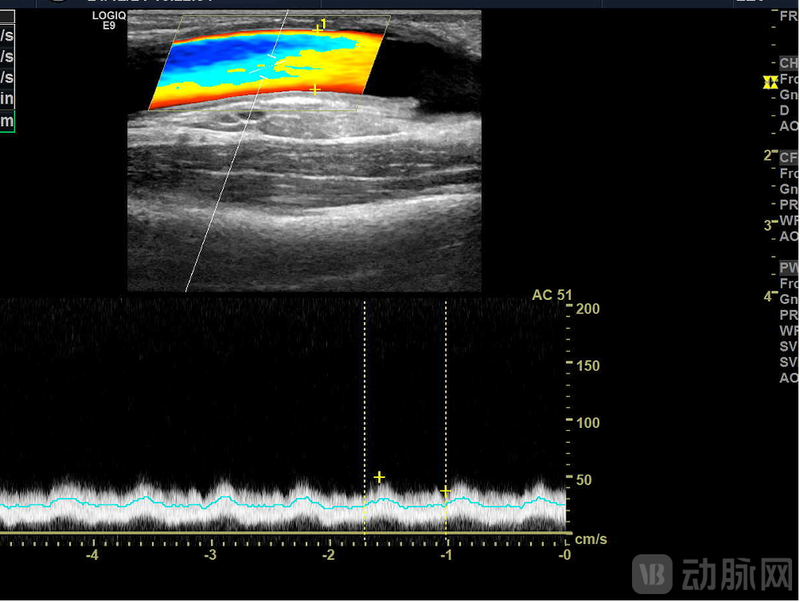

LineMatrix耐迈通®生物型人工血管植入患者体内6月超声随访管腔通畅